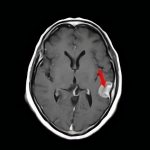

断層撮影

手術前1

手術前2